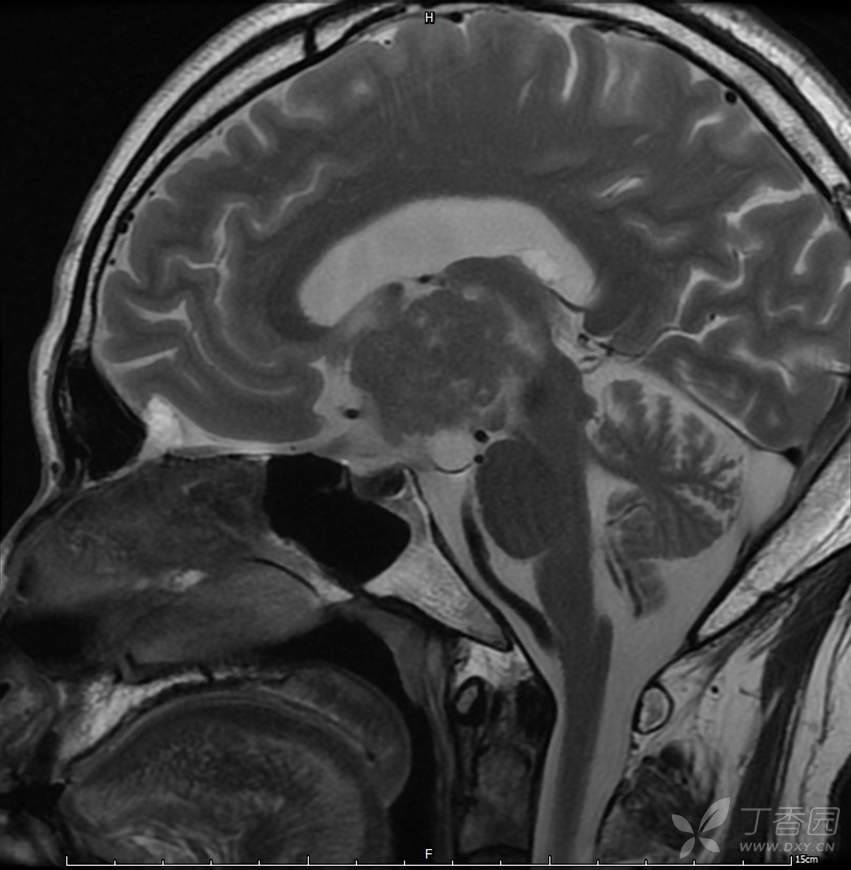

男,44岁,记忆力下降、乏力5月余,多尿3月余,CTMR全,疑难病例,能正确诊断吗?

图像不多,能诊断正确吗?有特征性吗?

T2WI